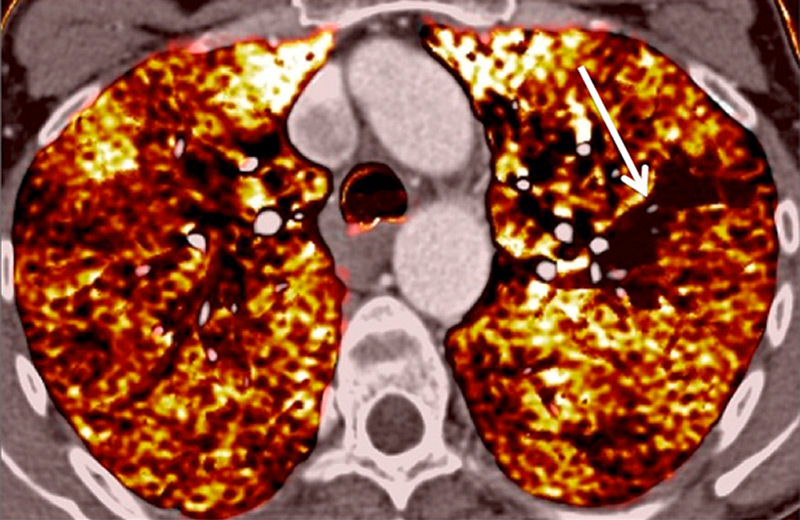

Figure 7

Portopulmonary hypertension in a 16-year-old. No abnormalities were found on morphological computed tomography (A/B), but heterogeneous perfusions were present on the perfusion map (stars, C/D).